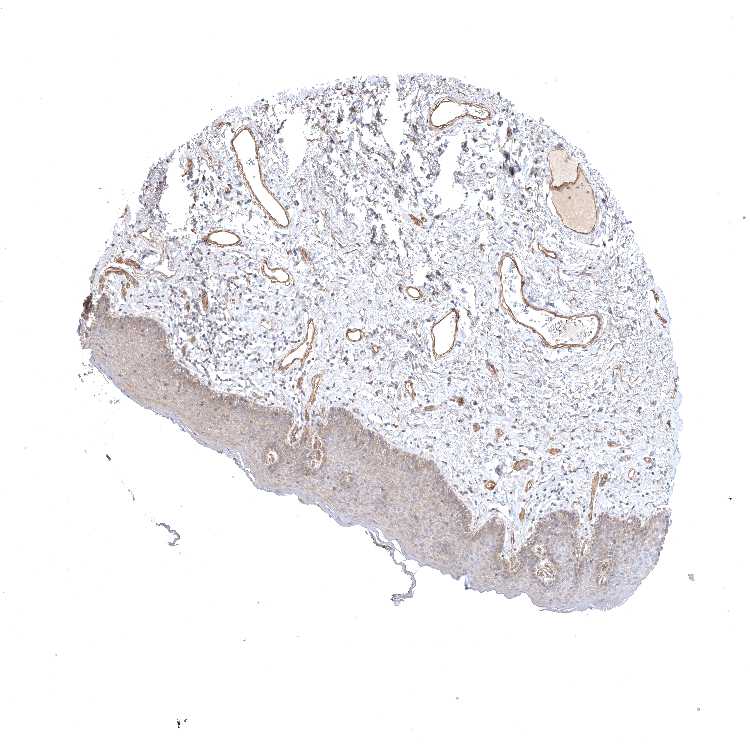

SKIN 1 - Antibody stainingi

Antibody staining in the annotated cell types in the current human tissue is reported as not detected, low, medium, or high, based on conventional immunohistochemistry profiling in selected tissues. This score is based on the combination of the staining intensity and fraction of stained cells.

Each image is clickable and will lead to virtual microscopy that enables deeper exploration of all samples and also displays staining intensity scores, fraction scores and subcellular localization as well as patient and tissue information for each sample.

Antibody HPA023584Antibody HPA024814

Langerhans HighNot detected

Fibroblasts MediumLow

Keratinocytes MediumLow

Melanocytes MediumNot detected

SKIN 2 - Antibody stainingi

Epidermal cells MediumMedium